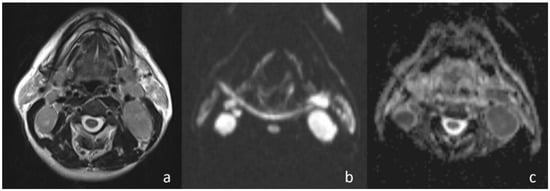

Figure 2. Pleomorphic adenoma of the parotid gland. (a) Axial T2-weighted image (T2WI) shows a mass in the left parotid gland; (b) the lesion shows low signal intensity on DWI; and (c) the mass is hyperintense on the ADC map (ADC value of 1.55 × 10−3 mm2/s).

In the current study, the mean ADC value of benign masses with high signal intensity was significantly (Figure 2) higher than that of malignant (Figure 3) masses with low signal intensity. These differences in ADC values may be explained by the differences in the histopathological characteristics of benign and malignant tumors. Generally, malignant tumors show hypercellularity and have enlarged nuclei, and hyperchromatism. These histopathological characteristics reduce the diffusion space of water protons in the extracellular and intracellular regions [13,14].